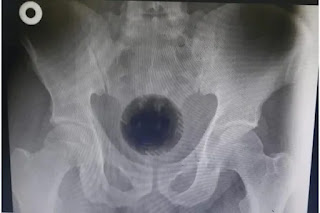

Texto: METROPOLES – Imagem: DivulgaçãoUm homem de 51 anos da Jordânia passou por uma cirurgia de emergência para retirar uma bola de plástico de 7 centímetros de diâmetro, equivalente ao tamanho de uma bola de tênis, que ficou presa no reto. Relatado no International Journal of Surgery Case Reports, o caso foi noticiado pelo jornal The Sun nesta terça-feira (13/9).

O paciente, que não teve o nome identificado, foi acompanhado pela

esposa ao Hospital Universitário Princess Basma, em Irbid, dois dias

depois do incidente, após tentativas frustradas de retirar a bola do

ânus com a ajuda de uma colher e uma chave de fenda.

A bola, que fazia parte de um aspirador de pó, ficou presa na pélvis

do paciente. Ele contou aos médicos que introduziu o objeto no próprio

corpo com a esperança de solucionar um problema de hemorroidas. A equipe

relatou, entretanto, não ter encontrado evidências desta condição de

saúde.